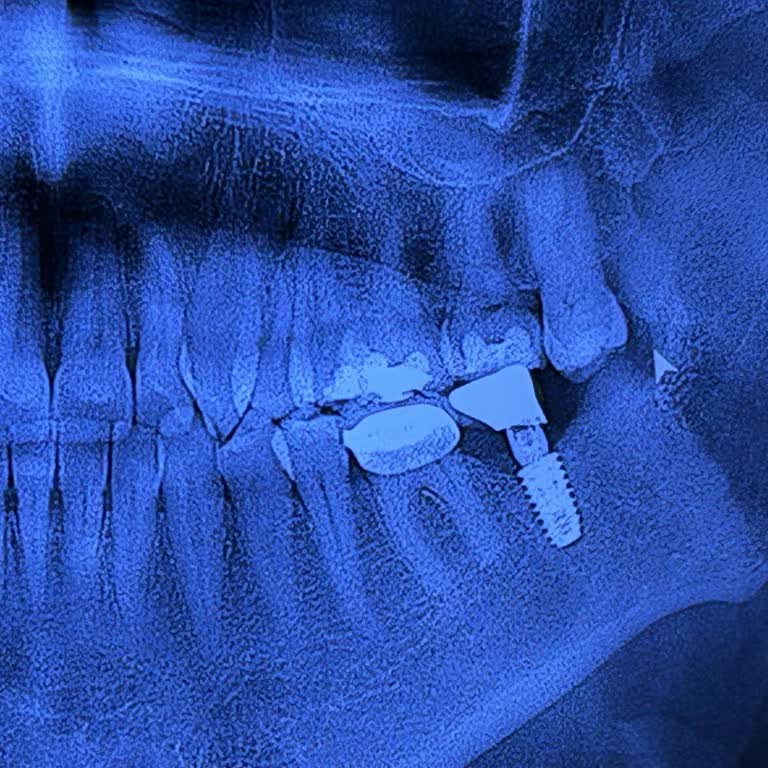

Ankara Batıkent Denta Center diş polikliniğinde doktor C**… tarafından eşimin diş tedavisi 4 implant uygulamasıyla yapıldı. Bir süre sonra yapıştırma etkisi olmayıp dişler yerinden çıkınca, bu kez 4 implantın yetersiz olduğu, 2 implant daha yapılması gerektiği söylendi ve yeniden ücret ödeyerek topl...

implant